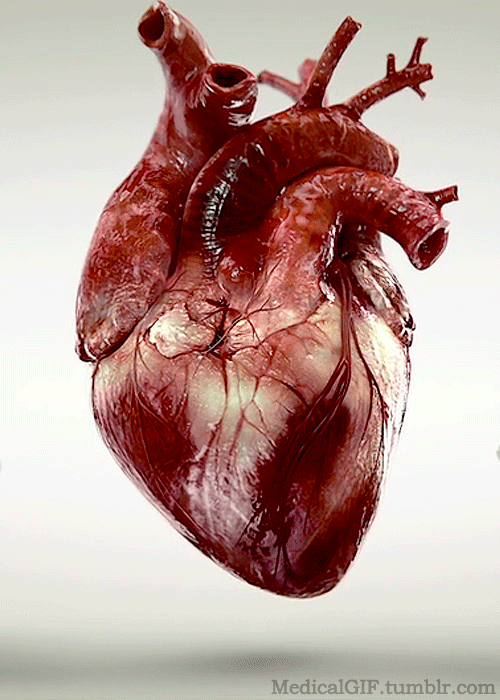

The Machine that Keeps the Heart Alive

Electrical Activity of the Heart